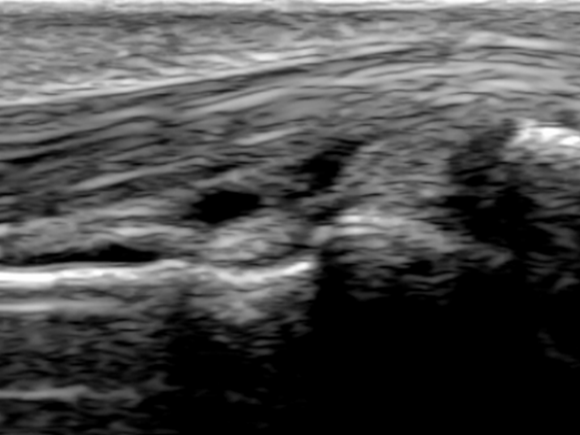

- X-ray, 초음파, MRI 등 영상검사

- 혈액검사(RF, anti-CCP 항체, ESR, CRP 등), X-ray, 초음파